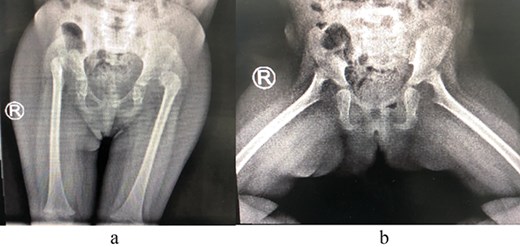

A 2-year-old girl was referred to our pediatric orthopedic clinic at XXX from a peripheral hospital for abnormal gait. On examination, the child had short stature and was thin. She had multiple dysmorphic features, which included a large head with frontal bossing and a triangularly shaped face, mid-face hypoplasia with depression in the nasal bridge and a fleshy nose tip, long philtrum, small pointy chin, micrognathia with large, prominent ears, and lordosis and waddling gait. A focused hip exam revealed bilateral limited hip abduction and leg length discrepancy. Images of the hips showed severe bilateral hip dysplasia (Fig. 1).

(a) Pre-operative AP view of the pelvis showing bilateral DDH. (b) Pre-operative frog-lateral view of the pelvis showing bilateral DDH.